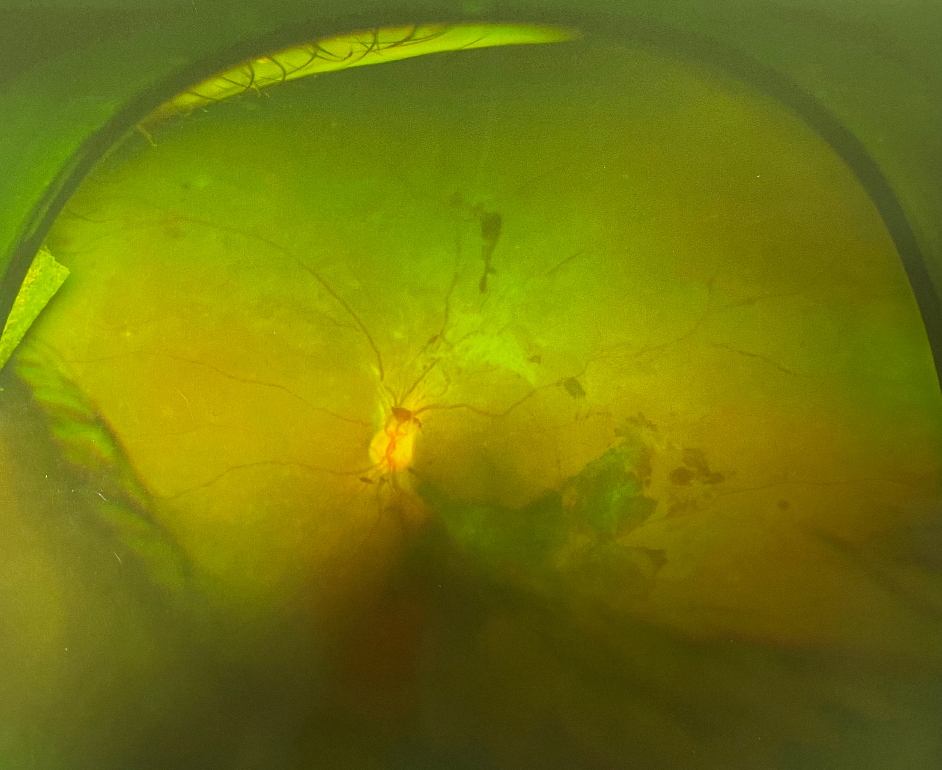

人眼的視網(wǎng)膜血管和脈絡(luò)膜血管系統(tǒng)保障供應(yīng)眼睛能量,并帶走其代謝產(chǎn)物。因此無(wú)論這些血管的哪一部分出問(wèn)題,都會(huì)影響視網(wǎng)膜的功能。眼底出血是指血液溢出血管到視網(wǎng)膜內(nèi)或周圍,若其范圍大或位于黃斑部則嚴(yán)重影響視力。這種出血需醫(yī)生通過(guò)眼底檢查方可看見(jiàn),一般人是無(wú)法看到的。眼底出血是眼科常見(jiàn)病,既可見(jiàn)于老年又可見(jiàn)于青少年,男女均會(huì)患病。

眼底出血

眼底出血多因高血壓、糖尿病、視網(wǎng)膜血管阻塞或免疫功能異常引起,常見(jiàn)于高血壓視網(wǎng)膜病變、糖尿病視網(wǎng)膜病變、視網(wǎng)膜靜脈阻塞,視網(wǎng)膜靜脈周圍炎性病變。

眼底出血是老年人的常見(jiàn)病,但常常被忽視,原因是其不易被發(fā)現(xiàn),在外觀上看不出來(lái),只能在醫(yī)院眼底鏡下被檢查出來(lái)。老年人易出現(xiàn)眼底出血,原因是老人的血管柔韌性和彈性發(fā)生改變,較硬且脆,稍有刺激便可能出血。伴高血壓、糖尿病、動(dòng)脈硬化、高脂血癥的病人,眼底血管硬化,應(yīng)特別注意。

眼底出血發(fā)生后病情的發(fā)展并非靜止不變,若未經(jīng)及時(shí)有效治療,出血不斷流人玻璃體腔,會(huì)導(dǎo)致玻璃體積血。出血停止后可通過(guò)自身的吸收功能將其吸收。出血量少,自身吸收功能好則可痊愈,反之溢出血管的血液成分會(huì)引發(fā)視網(wǎng)膜玻璃體的增殖,還會(huì)破壞周圍組織,造成視網(wǎng)膜缺氧,誘發(fā)新生血管等,從而引發(fā)嚴(yán)重并發(fā)癥——新生血管性青光眼,牽位性視網(wǎng)膜脫離等。所以發(fā)生眼底出血要盡早就醫(yī)。